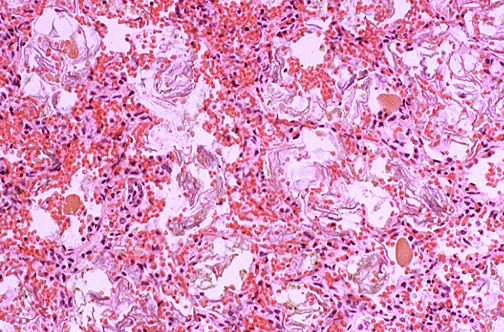

| Meconium spillage is a complication seen at or near term, typically when there is fetal distress with loss of anal sphincter tone and passage of meconium into amniotic fluid. A clue to this occurrence is greenish staining of fetal skin or fetal surface of the placenta. The worst consequence of meconium spillage is meconium aspiration into the lungs. Fetal distress also leads to reflex gasping efforts by the baby, with the result that the meconium in the amniotic cavity is aspirated into the lungs. Rugby ball shaped balls of meconium as well as numerous "squames" from fetal skin are seen here. |